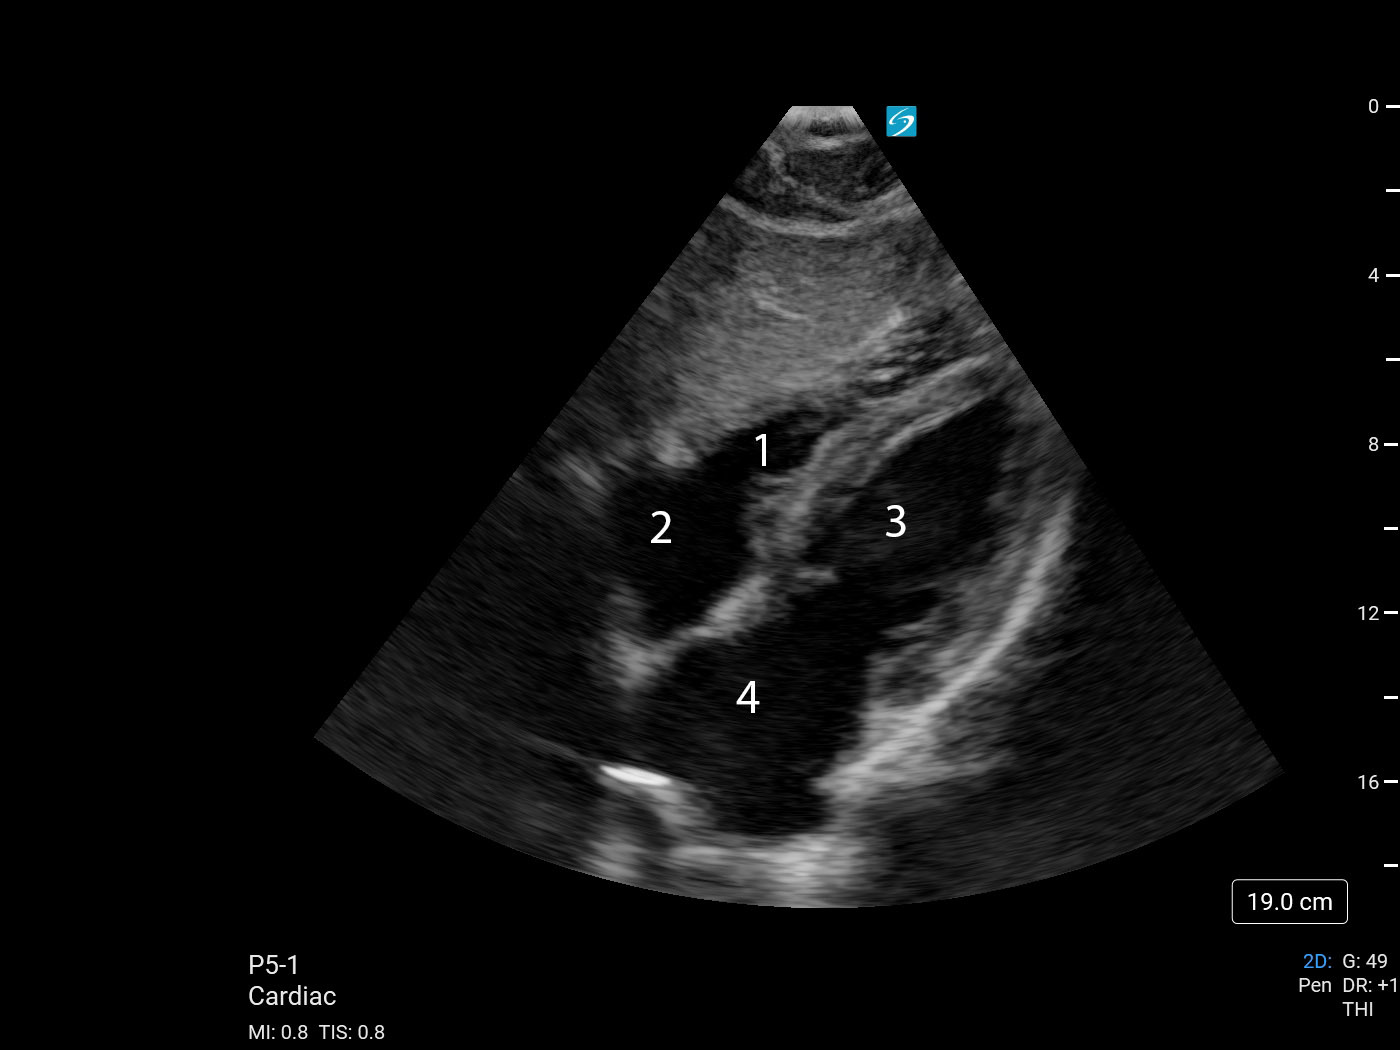

Heart Subcostal 4 Chamber View (Sonosite PX with P5-1) Image

1. Right Ventricle (RV)

2. Right Atrium (RA)

3. Left Atrium (LA)

4. Left Ventricle (LV)